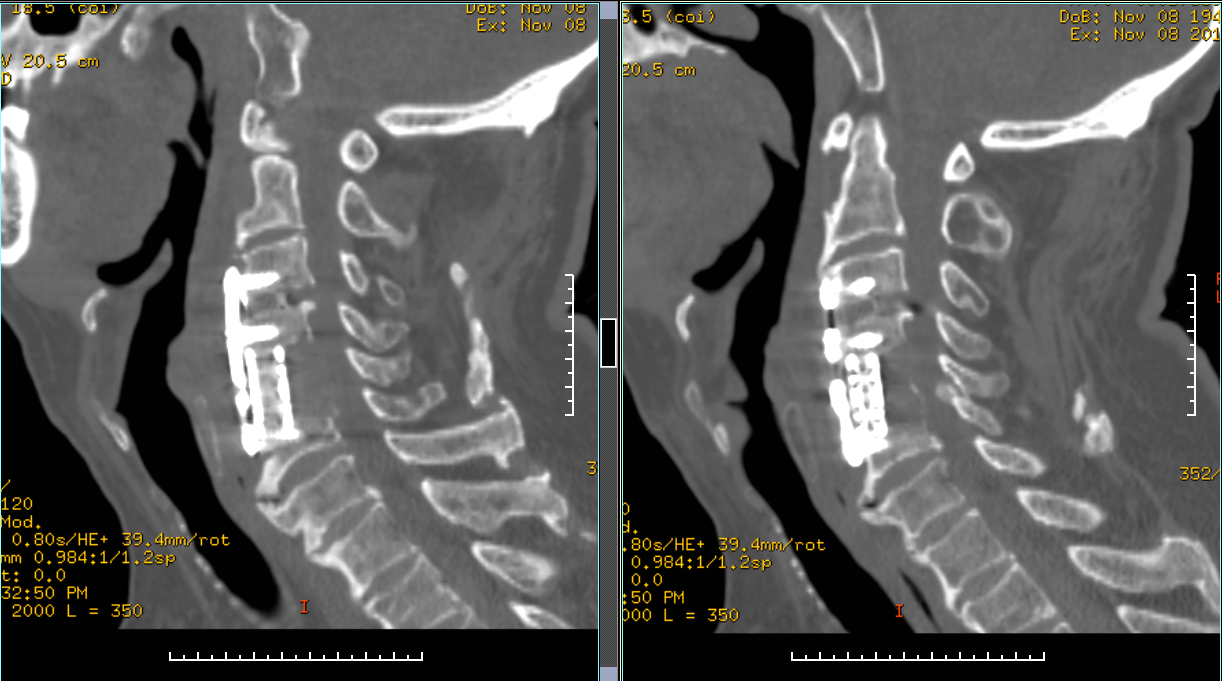

手术方案:显微镜辅助下颈椎后路全椎板减压内固定术

术后X线片

术后CT矢状位